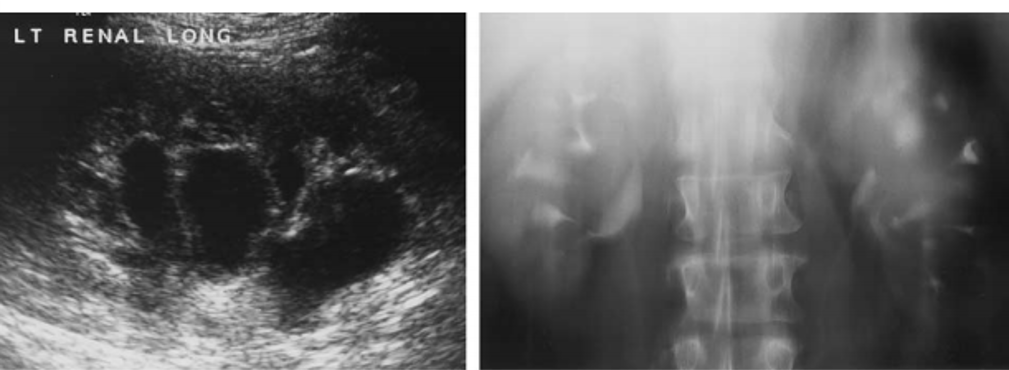

ureteritis cystica

medullary sponge kidney